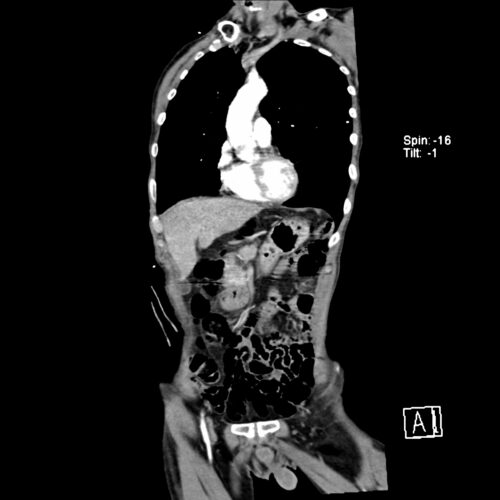

Für Männer über 65 Jahre wird die einmalige Ultraschall-Screeninguntersuchung auf Vorliegen eines Aneurysmas empfohlen. Aneurysmen zwischen 3 und 4cm sollten nach 12 Monaten, Aneurysmen zwischen 4 und 4,5cm nach 6 Monaten sonographisch kontrolliert werden. Ab einem Durchmesser von 4,5cm empfiehlt sich die Durchführung einer CT-Angiographie der Aorten-/Becken- und Beinstrombahn, die bei Aneurysmen bis 5cm jährlich wiederholt werden sollte.

Unverzichtbare Voraussetzung für eine endovasculäre Versorgung ist eine suffiziente Prothesenplanung. Nach Durchführung einer Dünnschicht-CT-Angiographie (Schichtdicke 1mm) von Aorta, Becken- und Beinstrombahn kann die Prothese mithilfe spezieller Messprogramme berechnet und/oder erstellt werden.

Erlaubt die Hämodynamik noch die Durchführung einer CT-Angiographie kann diese zur Diagnosestellung und Therapieplanung notfallmäßig vor Operation durchgeführt werden. Der hämodynamisch instabile Patient muss unmittelbar der operativen Versorgung zugeführt werden, ohne Verzögerung durch ein CT.